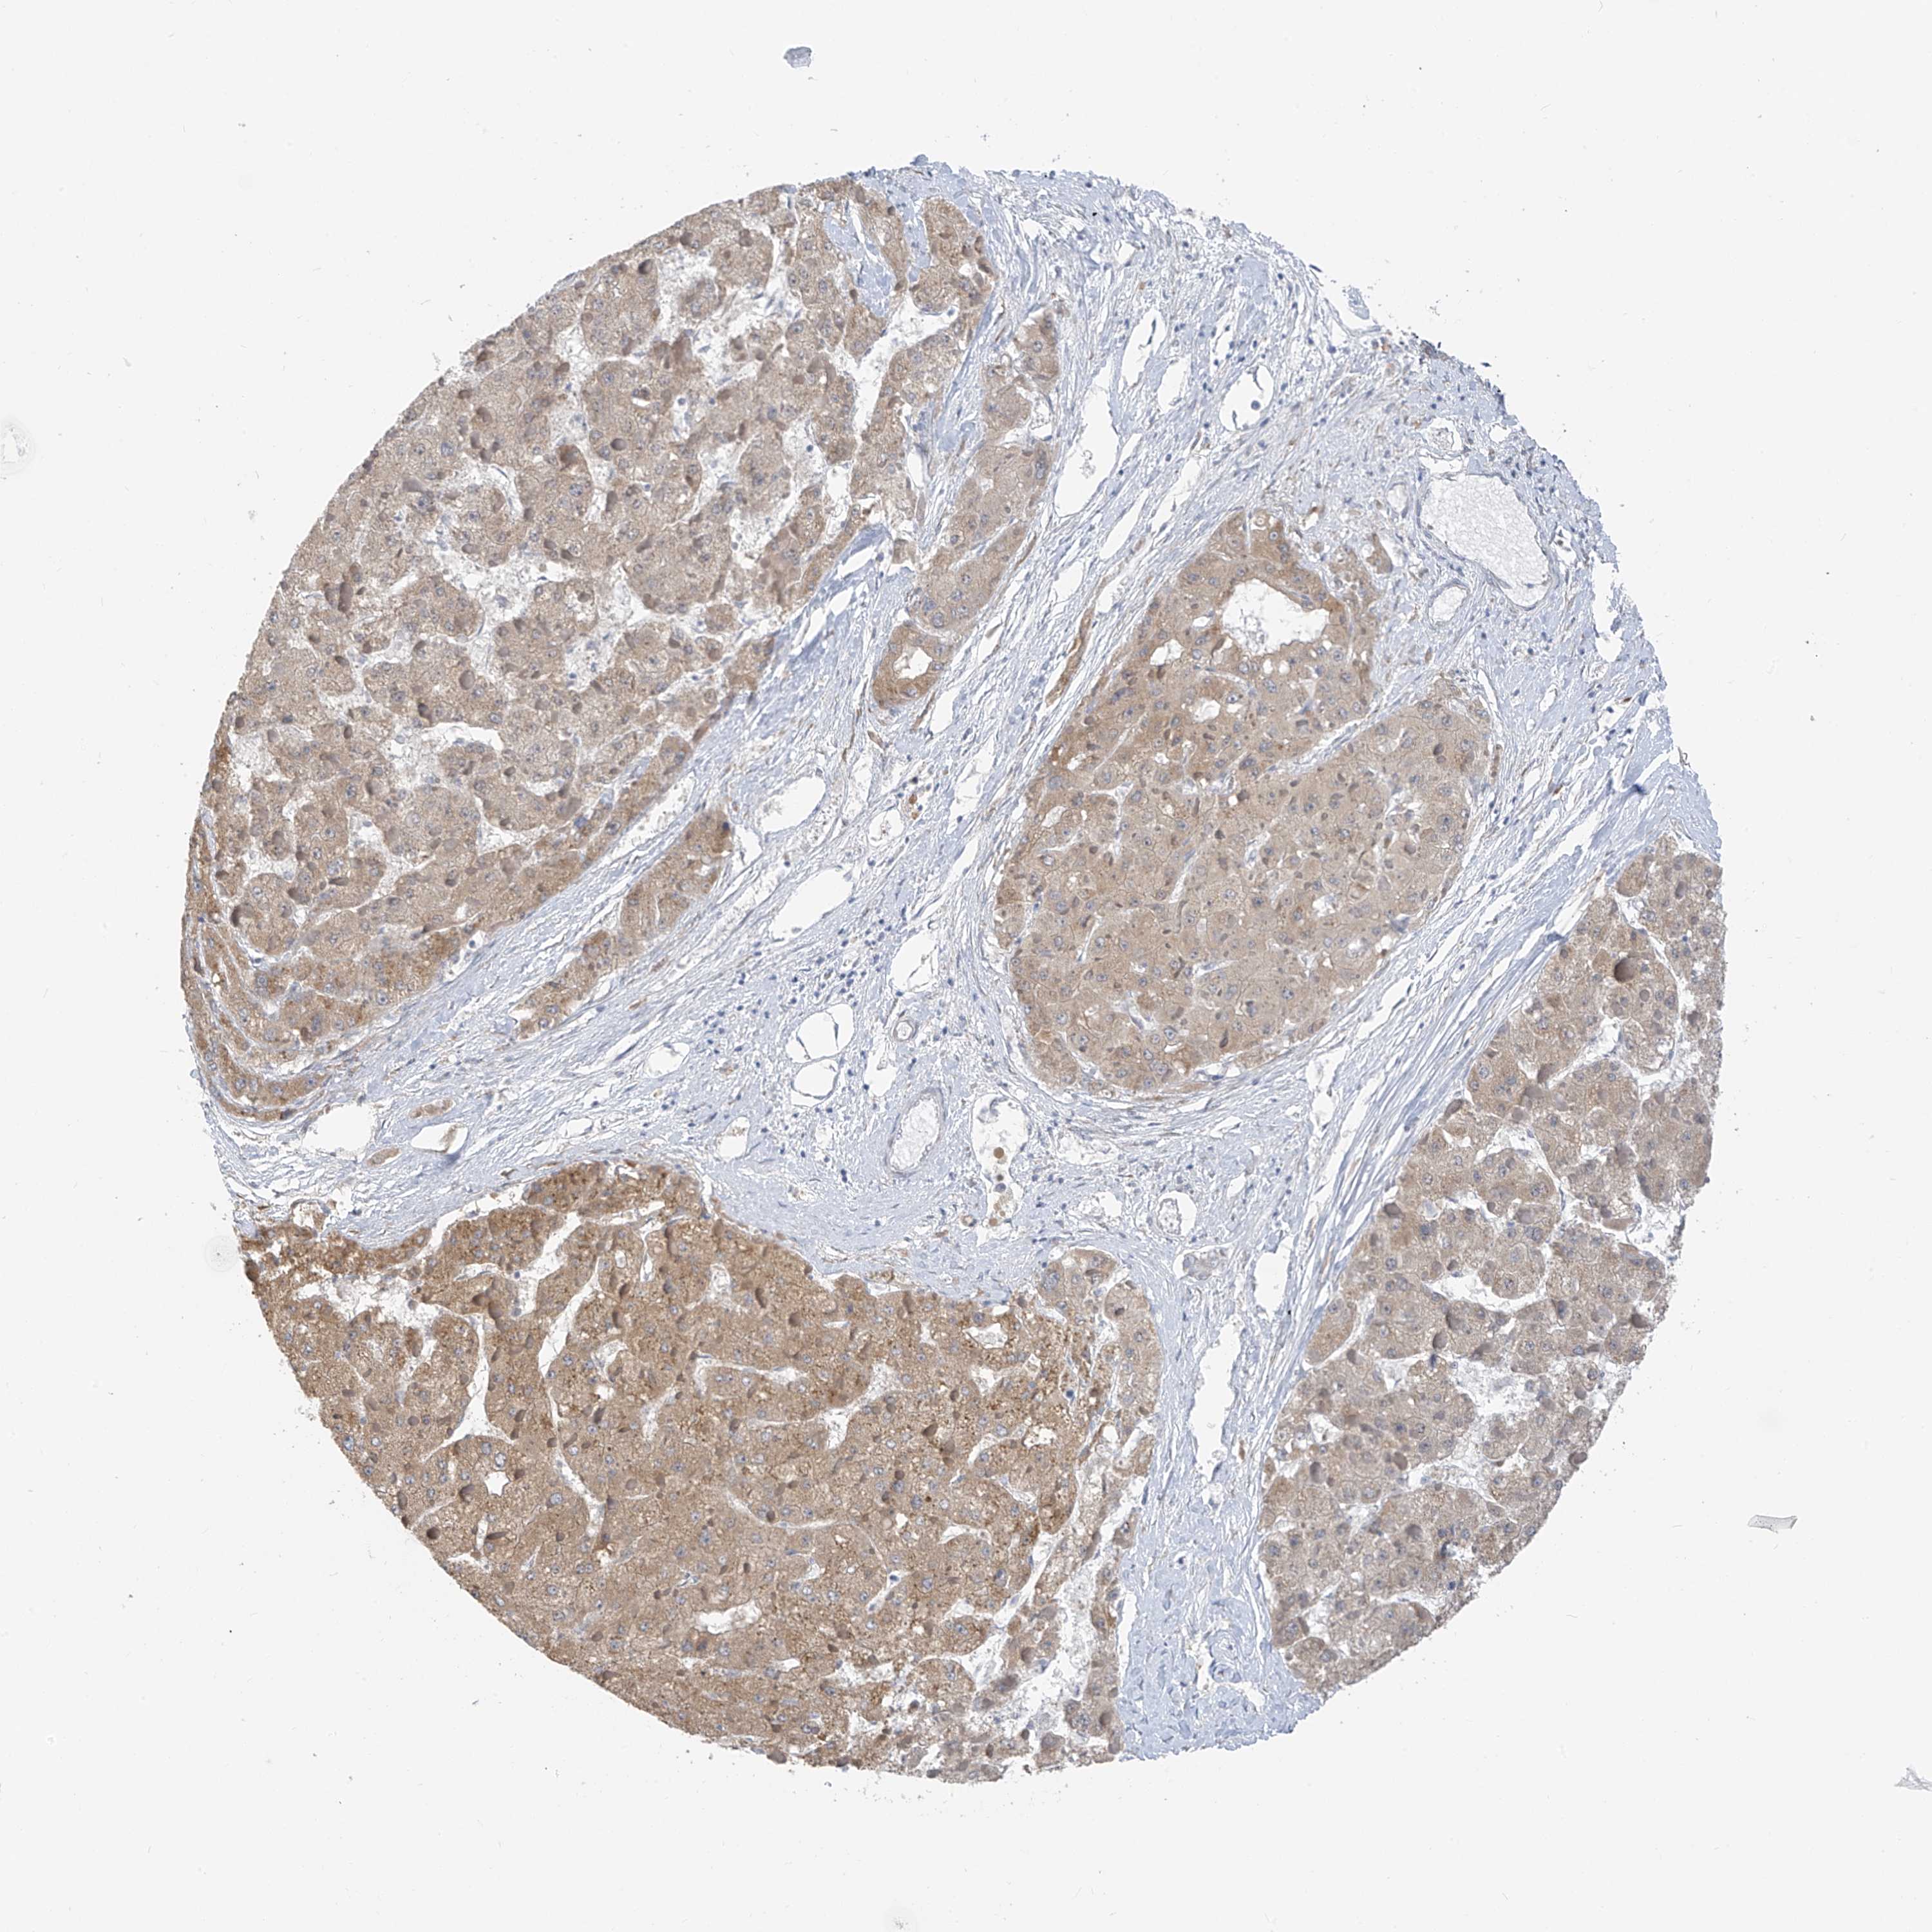

LIVER CANCER - Protein expressioni

A mouse-over function shows sample information and annotation data. Click on an image to view it in a full screen mode. Samples can be filtered based on level of antibody staining by selecting one or several of the following categories: high, medium, low and not detected. The assay and annotation is described here.

Note that samples used for immunohistochemistry by the Human Protein Atlas do not correspond to samples in the TCGA dataset.

Antibody stainingi

Antibody staining in the annotated cell types in the current human tissue is reported as not detected, low, medium, or high, based on conventional immunohistochemistry profiling in selected tissues. This score is based on the combination of the staining intensity and fraction of stained cells.

Each image is clickable and will lead to virtual microscopy that enables deeper exploration of all samples and also displays staining intensity scores, fraction scores and subcellular localization as well as patient and tissue information for each sample.

Antibody HPA029122

Staining

High

Medium

Low

Not detected

Intensity

Strong

Moderate

Weak

Negative

Quantity

>75%

75%-25%

<25%

None

Location

Nuclear

Cytoplasmic/membranous

Cytoplasmic/membranous,nuclear

Cholangiocarcinoma

Carcinoma, Hepatocellular, NOS